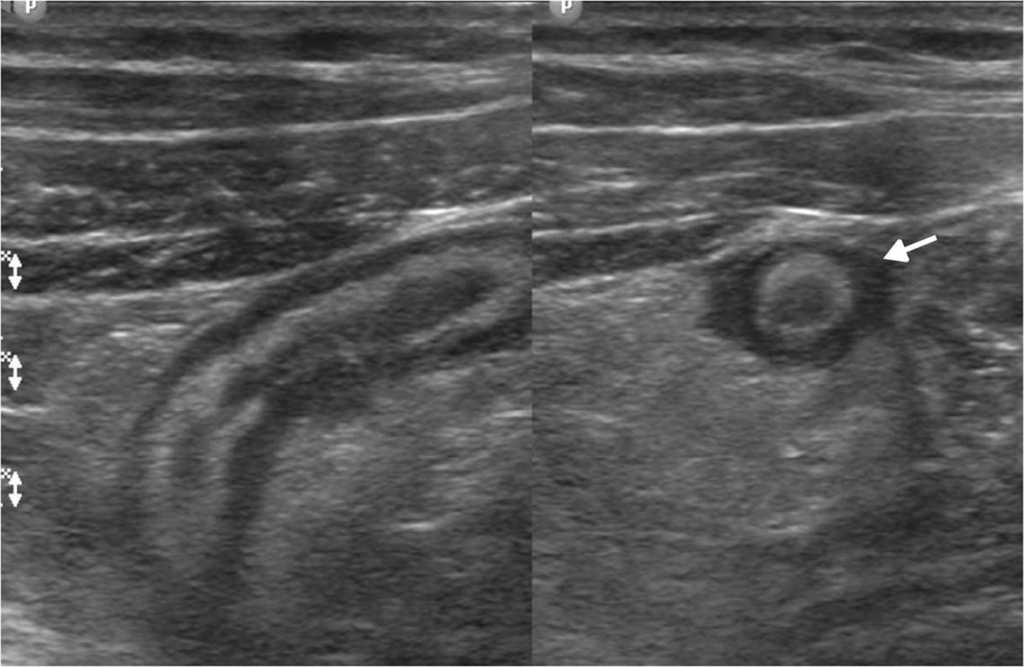

Las principales causas de esta dolencia son los quistes de ovario simples o hemorr??gicos, los embarazos ect??picos, las enfermedades inflamatorias pelvianas, las torsiones de ovario y otras patolog??as, muchas de las cuales tienen caracter??sticas ecogr??ficas propias que permiten su diagn??stico5 (figs. 1-3).

La ecograf??a determina la naturaleza s??lida o qu??stica de las masas anexiales, la presencia de septos o elementos s??lidos, y su vascularizaci??n con la exploraci??n Doppler (fig. 4). Estos hallazgos ayudan a determinar la benignidad o malignidad de la masa5,10.